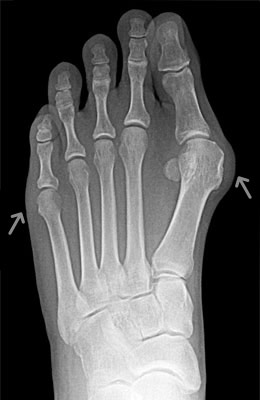

Before

After

Osteotomy Bunionectomy, Hammertoe Correction and Plantar Plate Repair after

Osteotomy Bunionectomy, Hammertoe Correction and Plantar Plate Repair

Ziba is a 67-year-old female with years of foot pain. Her bunion was so severe she had placed a lot of weight on her 2nd and 3rd toes which had become totally dislocated (as shown in x-rays). Ziba required an osteotomy bunionectomy, hammertoes corrections with our Ossio™ implant and metatarsal phalangeal joint relocation and plantar plate repair. Ziba was allowed to place weight on her foot right after surgery and was back in shoes at 8 weeks. An amazing result considering how difficult toe relocation can be. After picture taken immediately following surgery.